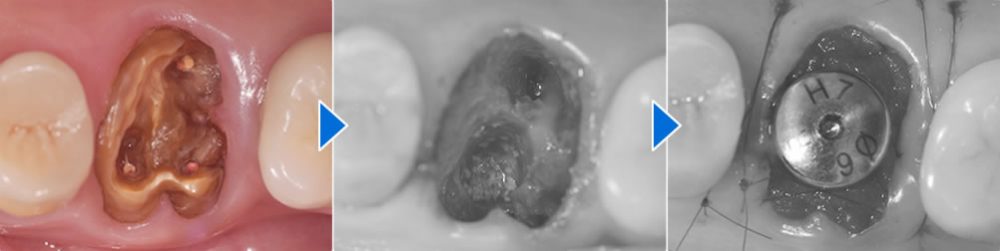

抜歯即時インプラントの実施

まず、残っていた歯根を丁寧に抜歯し、計画に沿ってインプラントを適切な位置に埋入しました。抜歯後に生じた骨の欠損部には、ソケットリフト(上顎洞挙上術)を行い、インプラントの埋入と同時に骨を補う骨造成も実施しました。